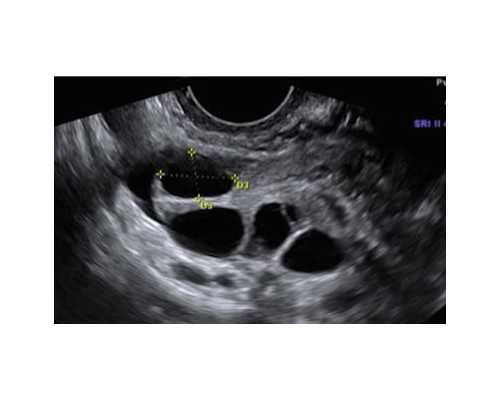

因为伴随胎儿形态的不断发展,DNA浓度会越来越高,并在受孕后7周达到高峰。所以验血要求之一即是孕满六周加三天,胚芽长度达5毫米;其它诸如半年内没流产过男胎,一年没生过男胎,没做过重大手术、输血等要求也需必备。

除了港澳通行证和b超单,不用带啥证件,港澳通行证要去你户口所在地的派出所办理,50块办一个,签证一次15块,办理的时候要带上身份证和照片,我去办理的时候不到一个星期就拿到了,跟身份证一样大小的卡片,港澳通行证在香港相当于我们的身份证,掉不得的,一定要保管好。B超单是验血用的,因为护士会看你孕期有没有满七周的哦。

A:达到周期后做B超确定

B:提前一到两天预约

C:带通行证和B超单去香港

D:到了验血机构后出示通行证和B超单给护士

E:护士确定后填表、付费、抽血

16周香港验血可以吗

F:等待结果(电子版通过网络发送,原件可自取,也可邮寄到家)